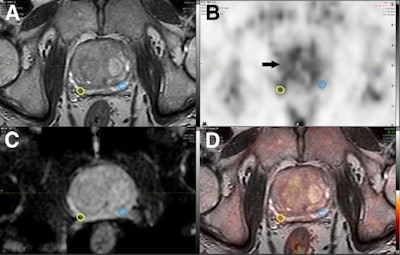

The images show coregistered axial 3D T2-weighted fast spin-echo MRI (A), choline-PET (B), apparent diffusion coefficient map (C), and PET/mpMRI (D). A small 0.16 cm3 right peripheral zone intermediate risk lesion (yellow circles) was confirmed as Gleason 4 + 4 cancer. Respective mirrored background volume of interest (blue circles) is shown, resulting in choline TBR of 1.61. Diffusely increased choline uptake is noted in benign prostate hyperplasia (arrow). Images courtesy of the Journal of Nuclear Medicine.Modality accuracy